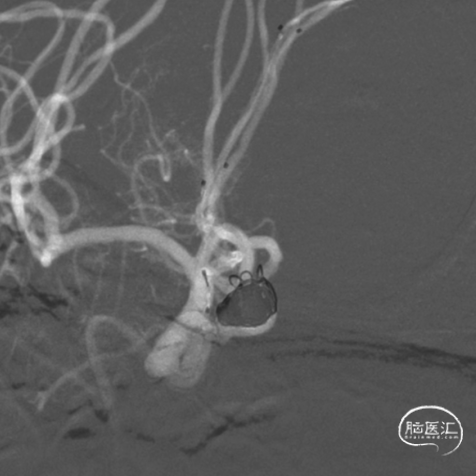

置入第一枚Atlas支架 3mm×15mm。

置入第二枚Atlas支架 4mm×21mm。

造影示“T”型支架左侧Atlas支架 3mm*15mm 、右侧 Atlas支架 4mm*21mm,动脉瘤致密栓塞,不显影。双侧A2段显影良好。